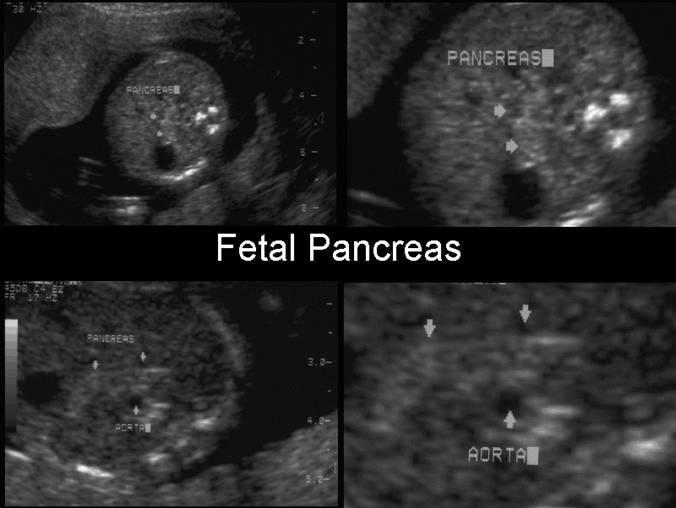

Pancreas

annular pancreas

What is an annular pancreas?

extension of pancreas tissue around duodenal

forming a ring

What problems does annular pancreas cause in infants?

feeding problems

reflux and vomiting